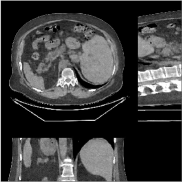

Fig.Β 10 shows the reconstructions (shown for the central axial, sagittal, and coronal planes in the 3D volume) for PWLS-EP and PWLS-ULTRA with patch-based weights () from low-dose abdomen scans. For the sagittal and coronal planes, we show the central out of axial slices. The supplement provides PWLS-EP reconstructions with different regularization strengths. The PWLS-ULTRA reconstructions in Fig.Β 10 have reduced noise as well as higher resolution, better structural details and shaper image edges than the PWLS-EP results. These results are further example of the potential performance of the proposed PWLS-ULTRA method in clinical settings.